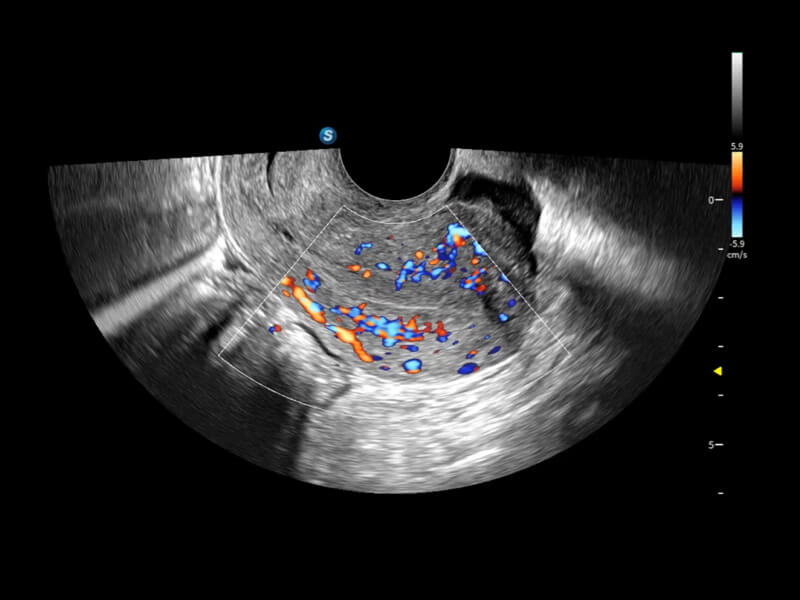

• HyCoSy mit SPI ermöglicht eine intuitivere und sensitivere Bilddarstellung. Es zeigt klar, wie lange das Kontrastmittel benötigt, um verschiedene Bereiche der Gebärmutter, Eileiter und Eierstöcke zu erreichen. Dadurch erhalten Kliniker fundierte und zuverlässige Nachweise bei der Untersuchung der Eileiterdurchgängigkeit bei unfruchtbaren Frauen.